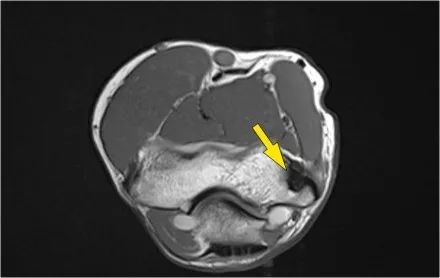

当您寻找桡侧副韧带时,首先要尝试识别常见的伸肌腱,因为在它下面你会发现桡侧副韧带(黄色箭头)。

当你向后走时,你会看到LUCL--侧面尺侧副韧带,它在桡骨头后面扫过(白色箭头)。环形韧带通常难以与RCL区分开,但有时可以在矢状MR-关节造影上识别。

我们可以从连续的冠状位MRI图像观察。

常见的伸肌腱起源于外上髁。在T1W图像上,肌腱应具有低信号强度(黄色箭头)。